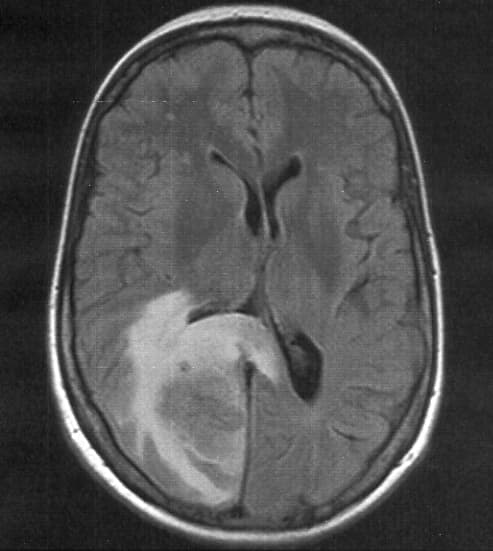

Cerebral edema is excess accumulation of fluid (edema) in the intracellular or extracellular spaces of the brain. This typically causes impaired nerve function, increased pressure within the skull, and can eventually lead to direct compression of brain tissue and blood vessels. Symptoms vary based on the location and extent of edema and generally include headaches, nausea, vomiting, seizures, drowsiness, visual disturbances, dizziness, and in severe cases, coma and death. Cerebral edema is commonly seen in a variety of brain injuries including ischemic stroke, subarachnoid hemorrhage, traumatic brain injury, subdural, epidural, or intracerebral hematoma, hydrocephalus, brain cancer, brain infections, low blood sodium levels, high altitude, and acute liver failure. Diagnosis is based on symptoms and physical examination findings and confirmed by serial neuroimaging (computed tomography scans and magnetic resonance imaging). The treatment of cerebral edema depends on the cause and includes monitoring of the person's airway and intracranial pressure, proper positioning, controlled hyperventilation, medications, fluid management, steroids. Extensive cerebral edema can also be treated surgically with a decompressive craniectomy. Cerebral edema is a major cause of brain damage and contributes significantly to the mortality of ischemic strokes and traumatic brain injuries. As cerebral edema is present with many common cerebral pathologies, the epidemiology of the disease is not easily defined. The incidence of this disorder should be considered in terms of its potential causes and is present in most cases of traumatic brain injury, central nervous system tumors, brain ischemia, and intracerebral hemorrhage. For example, malignant brain edema was present in roughly 31% of people with ischemic strokes within 30 days after onset. The extent and severity of the symptoms of cerebral edema depend on the exact etiology but are generally related to an acute increase of the pressure within the skull.